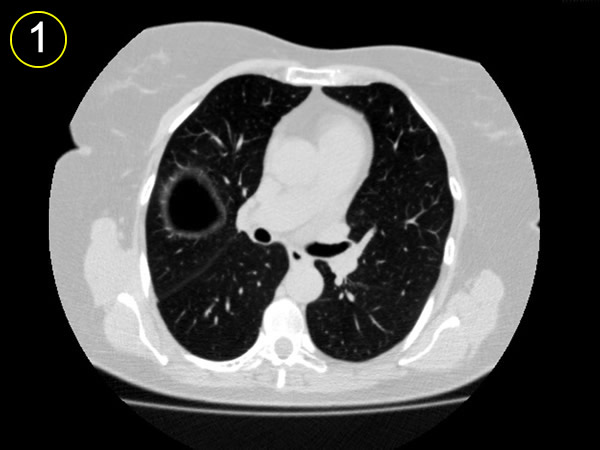

La tomografía

computarizada del tórax

y su adecuada interpretación es de gran ayuda diagnóstica

en las patologias del tórax.